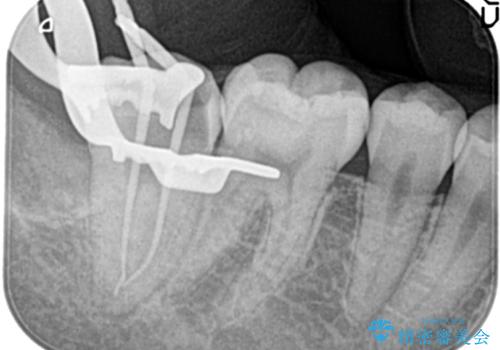

- 3日前からズキズキ痛み、冷たいものや熱いもので持続痛もあるとのこと。

不可逆性歯髄炎の診断で抜髄処置を行なっています。

根管治療は1回ごとにまとまった時間で治療を行うことにより2~3回の治療で完了します。

根管治療した歯は、クラウン修復が必要です。